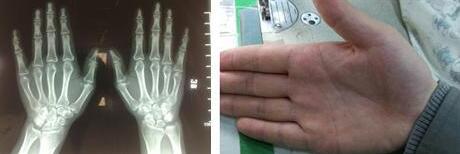

6年前,胡女士手指突然剧烈疼痛,像是被蚂蚁啃噬的那种钻心的痛。休息后按摩了好久才好不容易恢复了知觉。可是渐渐的发现,手指不仅痛,还红肿了起来。到医院做了检查,诊断为类风湿性关节炎。此后接受药物...[详细]